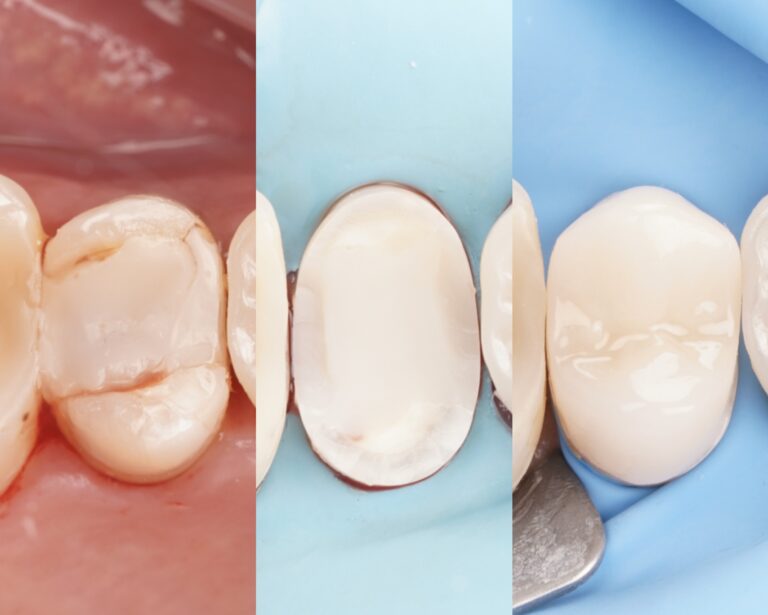

Zdrowa i żywa miazga jest kluczowym czynnikiem warunkującym długoterminową przeżywalność zęba. Odpowiada za prawidłowe odżywianie zmineralizowanych tkanek oraz stanowi naturalną barierę ochronną przed wtargnięciem drobnoustrojów. Celem leczenia biologicznego jest utrzymanie żywej, zdrowej miazgi poprzez stymulację jej komórek do produkcji zębiny reparacyjnej.

Biodentine wyróżnia się wyjątkową skutecznością w leczeniu głębokich ubytków próchnicowych, minimalizując ryzyko powikłań i często eliminując konieczność leczenia kanałowego.

Biodentine to nowoczesny materiał bioaktywny, który dzięki swoim unikalnym właściwościom wspiera regenerację miazgi i odbudowę zębiny. Jego wszechstronność, biokompatybilność oraz doskonałe właściwości mechaniczne sprawiają, że jest cennym narzędziem w codziennej praktyce stomatologicznej.